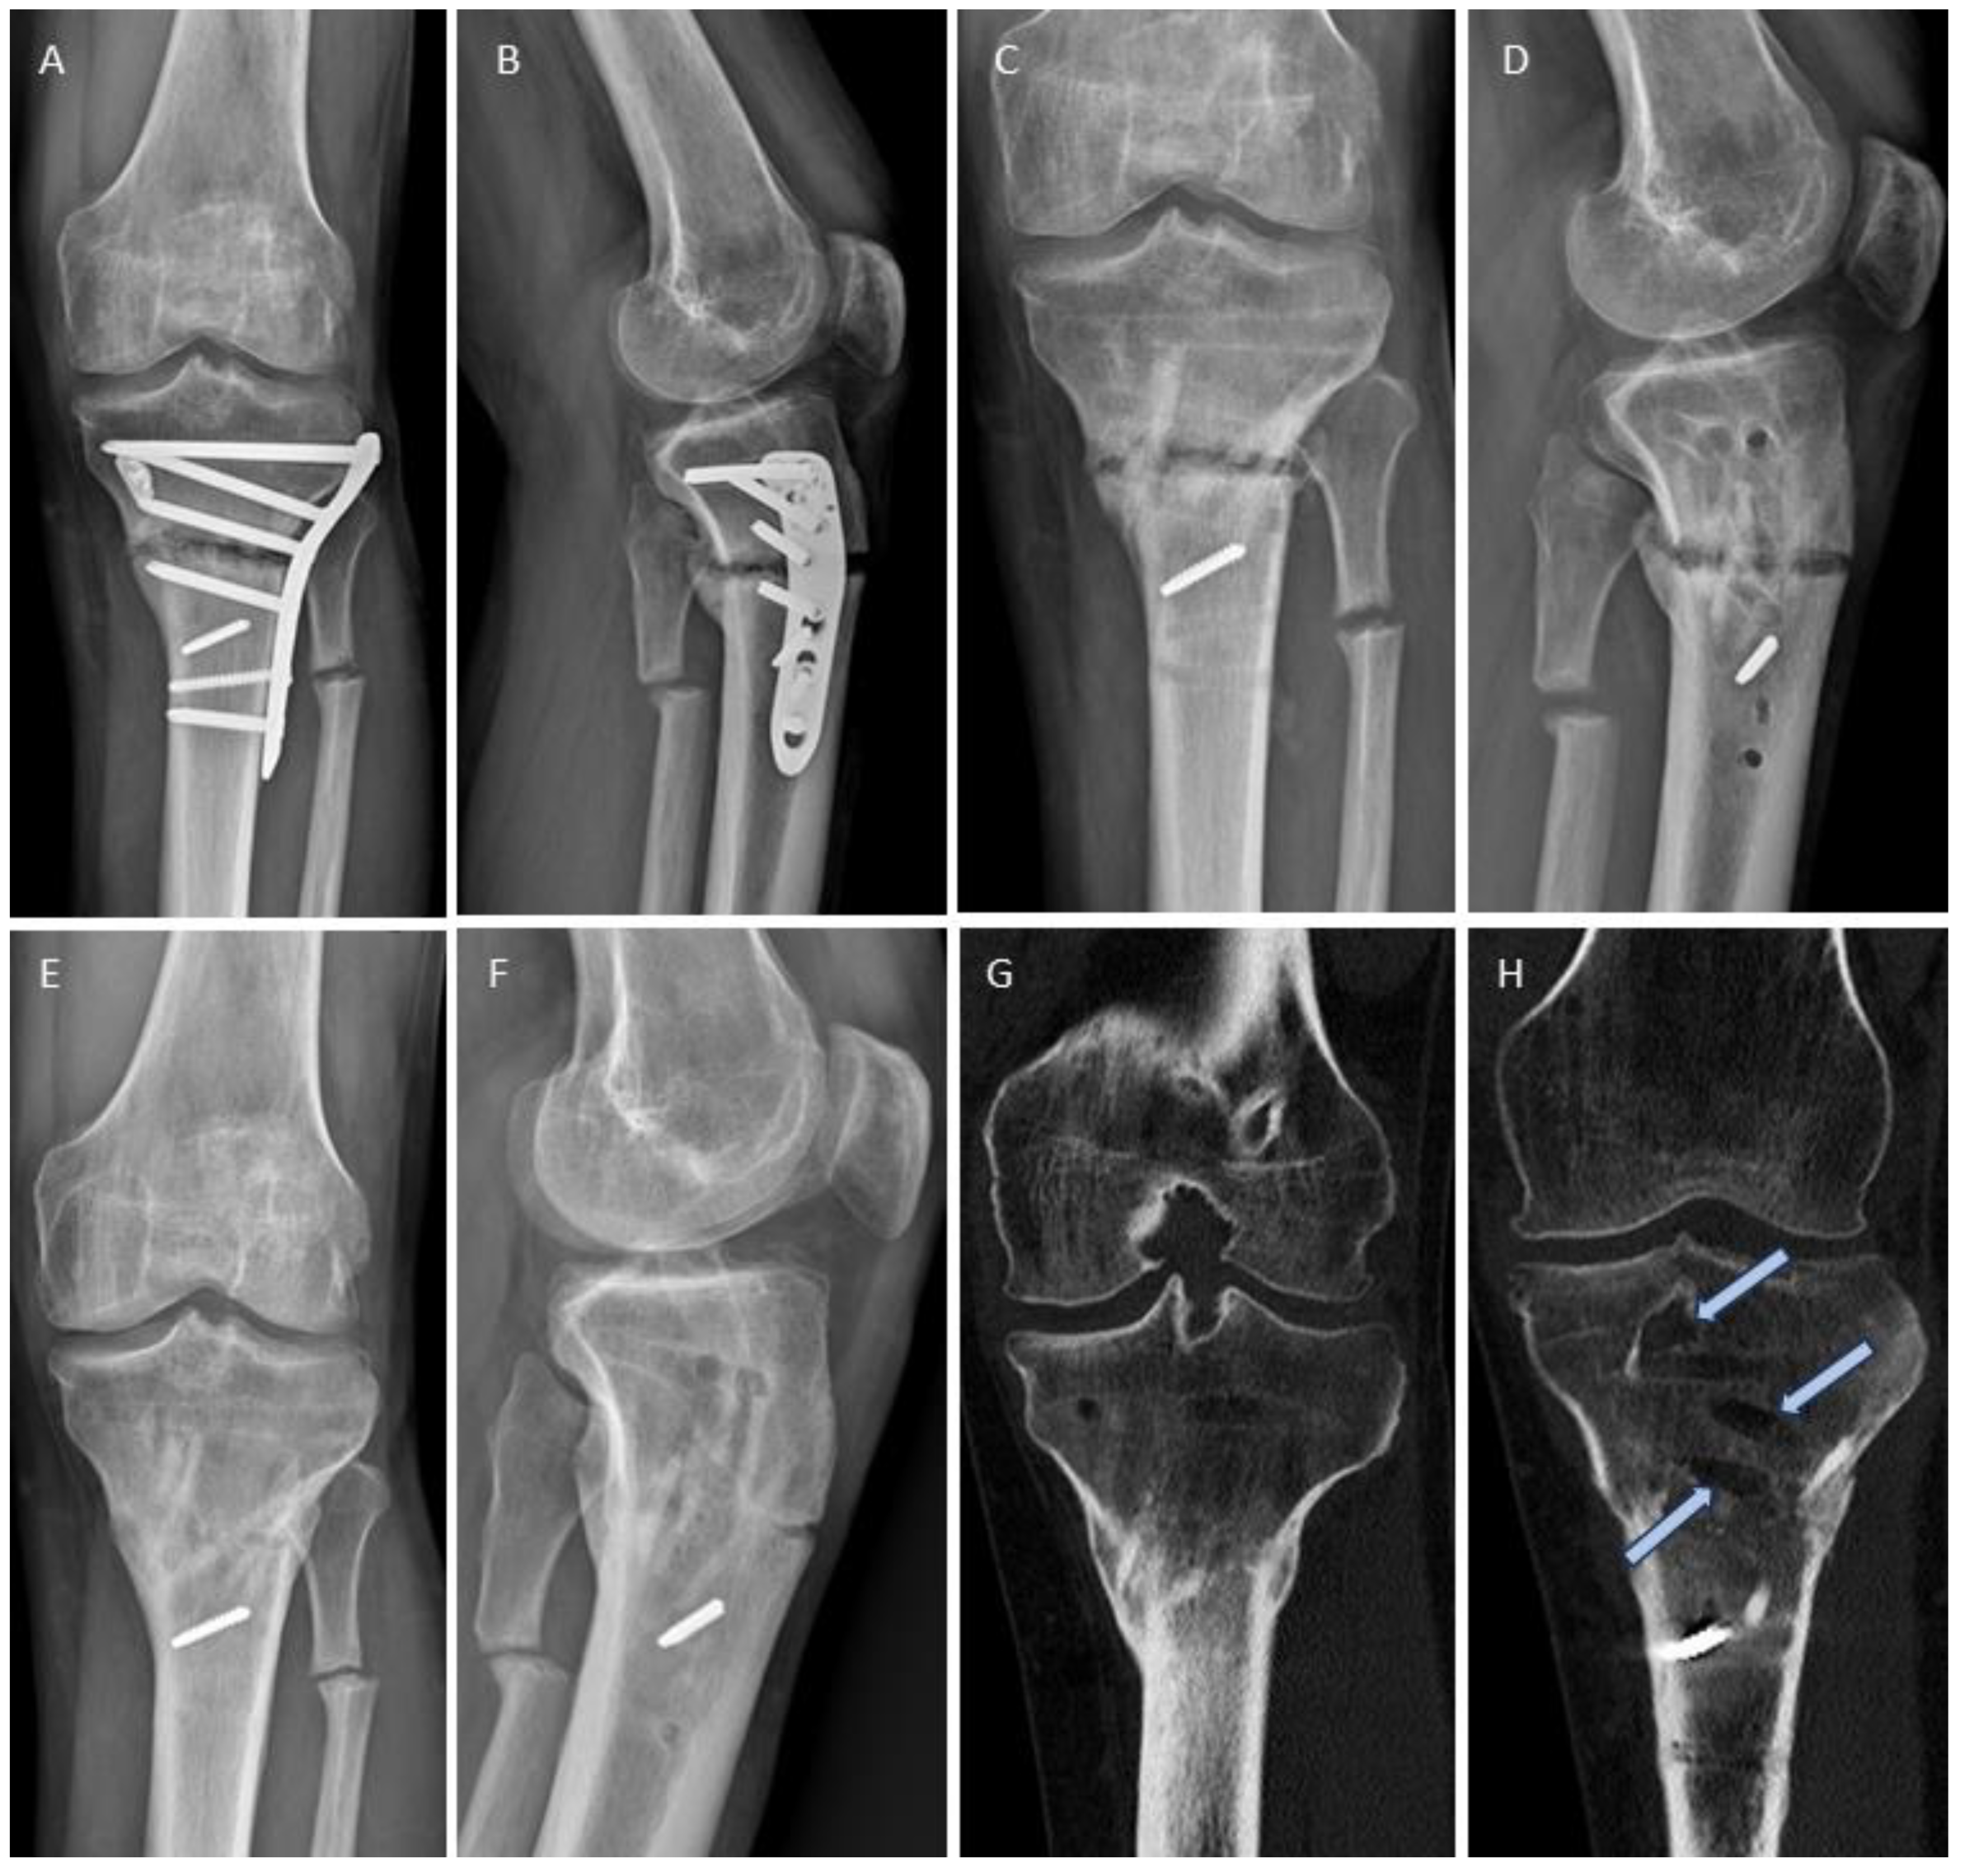

3.4. Examples for Bone Healing

3.6. Radiological Findings of Interest